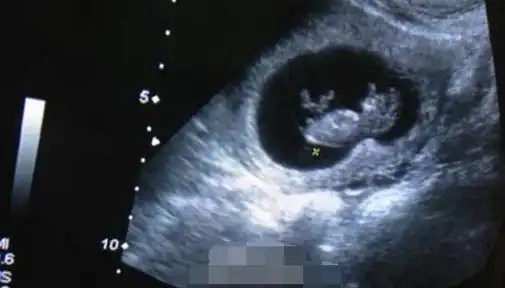

欧弟晒妻子怀孕b超照:跟老天爷又申请一个账号